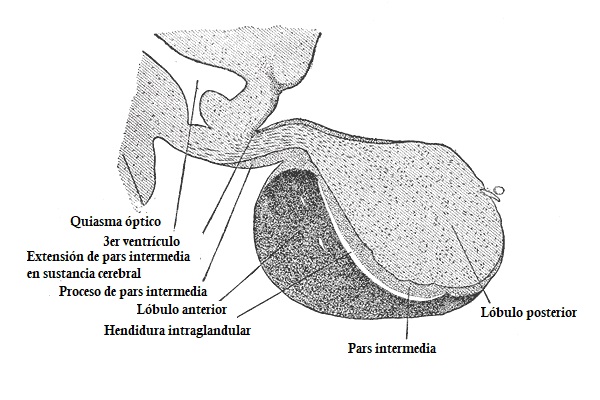

Anatómicamente, la hipófisis puede dividirse en tres grandes regiones: el lóbulo anterior o adenohipófisis, la hipófisis media o parte intermedia y el lóbulo posterior o neurohipófisis.

Hipófisis media

La hipófisis media es una región estrecha de la hipófisis que actúa como límite entre su lóbulo anterior y su lóbulo posterior. Posee un tamaño pequeño (aproximadamente el 2% del tamaño total de la glándula pituitaria) y proviene de la bolsa de rathke.

La hipófisis media se caracteriza por presentar una función diferente a la del resto de regiones de la hipófisis. Está formada tanto por células reticulares como por células estrelladas, un coloide y un epitelio de células cúbicas que lo rodea.

Así mismo, la hipófisis media contienen otras células con formas ovaladas, las cuales poseen gránulos en su parte superior. Estas células se encargan de segregar la hormona estimulante de melanocitos.

La hipófisis media se encuentra encima de los capilares, por lo que permite un tránsito más rápido y efectivo de la hormona al torrente sanguíneo.

Neurohipófisis

Finalmente, la neurohipófisis constituye el lóbulo posterior de la hipófisis. A diferencia de las otras dos partes de la hipófisis, no presenta un origen ectodérmico, ya que esta se forma a través de un crecimiento hacia abajo del hipotálamo.

La neurohipófisis puede dividirse en tres partes: la eminencia media, el infundibulo y la pars nervosa. Esta última es la región más funcional de la neurohipófisis.

Las células de la neurohipófisis son células gliales de sostén Por este motivo, la neurohipófisis no constituye una glándula secretora, ya que su funcionamiento se limita a almacenar los productos de secreción del hipotálamo.